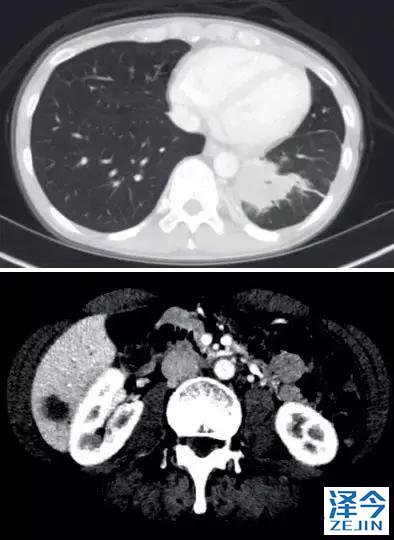

一位77岁的女性患有EPS15-NTRK1 IV期非小细胞肺癌,我们可以看到她的双肺满是病灶,并且出现了肝脏和脑转移,可以说是非常非常晚期了,

肺靶病变达到缓解,我们可以明显的看到前后的图像,病灶明显缩小了,

初始, 2018年6月 3周期 2018年8月